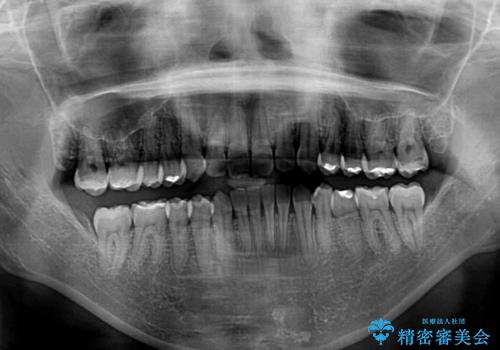

- 上下の前歯のデコボコと奥歯の反対咬合を気にして来院された患者様です。

インビザラインを用い、上下顎ともにIPR(歯と歯の間を削る)により叢生を改善することとしました。

奥歯の反対咬合は、骨格に由来するものであるため、改善できるところまで改善していくこととしました。